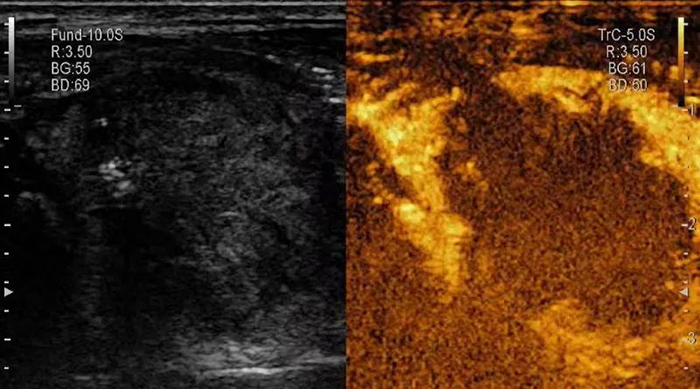

▲消融前,超声造影提示甲状腺结节内部血供丰富,活性大。

▲消融后,超声造影提示结节内完全无增强,呈“黑洞征”,表明肿瘤被完全杀死。